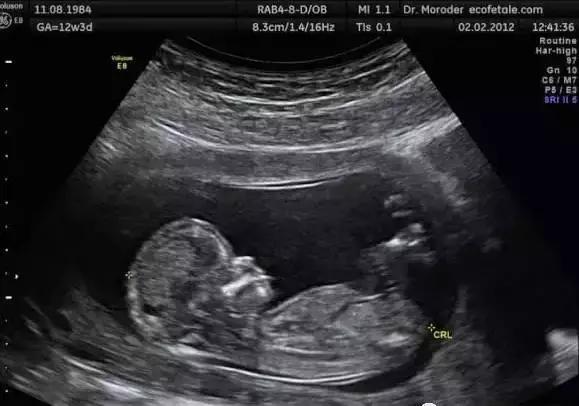

这名法国宝宝似乎太过好动,竟然在胎动的过程中一脚踢破妈妈的子宫,超声检查影像出来时,当场震惊了医师和母亲本人。

生命力惊人的小宝宝在妈妈的肚子里面不断的表现出惊人的活泼,没想到在妈妈某次产检时竟发现小脚丫已经踢破子宫,但因为孕妇没有任何不适,所以一直都没有发现。

法国一名医生表示,这是一起罕见的个案,他自己从来没有遇过这样的情形,医学上记录也只有26起。分析是因为这名孕妇已经第6次怀孕,过去5次是剖腹生产增加了子宫壁撕裂的风险。

由于剖腹产会留下疤痕,疤痕位置变得很厚,但周遭会变得脆弱,怀孕所承受的压力会让子宫壁变得更薄甚至撕裂,若是婴儿活动力较强,的确有可能就踢破了。

该名妈妈的磁共振扫描(MRI)照片可以看到,箭头所指之处就是宝宝的双脚,而子宫壁处在怀孕初期已有2.5cm大的撕裂,使得部分装着发育中宝宝的羊膜囊露出子宫,宝宝也因为胎动刚好把脚伸出去,造成惊人的景象。

医生表示,通常子宫壁撕裂对导致疼痛与出血,但宝宝的脚伸出去刚好可以帮忙止血,当时发现时,子宫壁已经增加撕裂到5cm,宝宝的双脚跟腹部都已经在子宫外,随即进行剖腹生产,所幸母子均安。